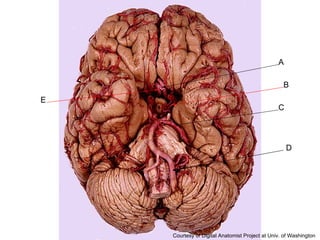

E B C D A

Answer Key A: corpus callosum B: extreme capsule C: globus pallidus D: claustrum E: caudate nucleus